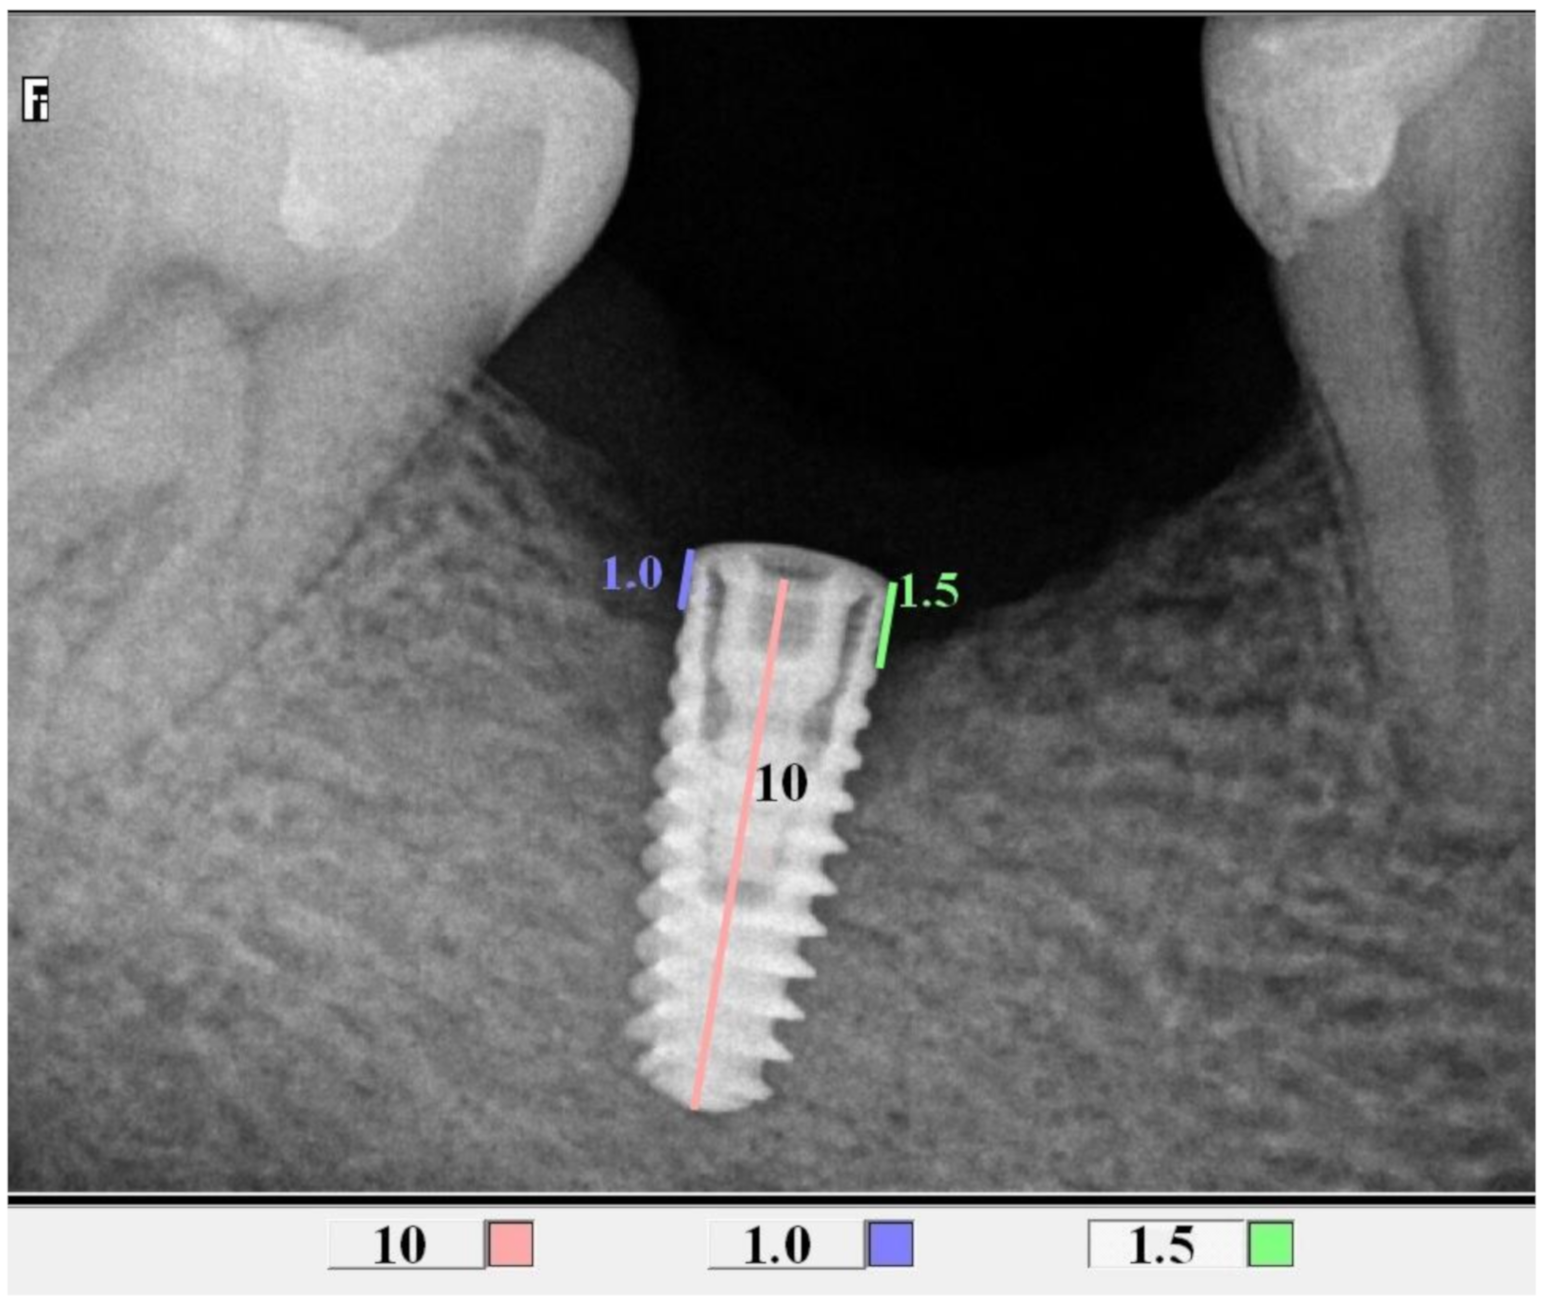

All control tests were performed by the second operator (GT). The evaluation of bone loss/growth was performed on the basis of radiovisiography (RVG) images taken with the long cone paralleling technique using a positioner (Figure 1). The bone level in the immediate proximity of the implant was determined using the RVG image analysis. Three targeted radiographic images were compared on the day of implantation, and after six and twelve weeks. Bone tissue loss or growth were assessed using software designed for analyzing digital radiovisiography. The calculated value was the arithmetical mean of the measurements performed on both sides of the implant that were visible in the two-dimensional image (the calculations were made starting at the head of the closing screw). To enable effective calibration, a measurement was made along the long axis of the implant (a) (Figure 2, Figure 3 and Figure 4), which was related to its actual length (y) and was calculated from Formula (1) as follows:

Figure 2.

Measurements of bone loss in the proximity of the implant (DIS, dental image software).

Figure 3.

Measurements of bone growth in the proximity of the implant (DIS, dental image software).